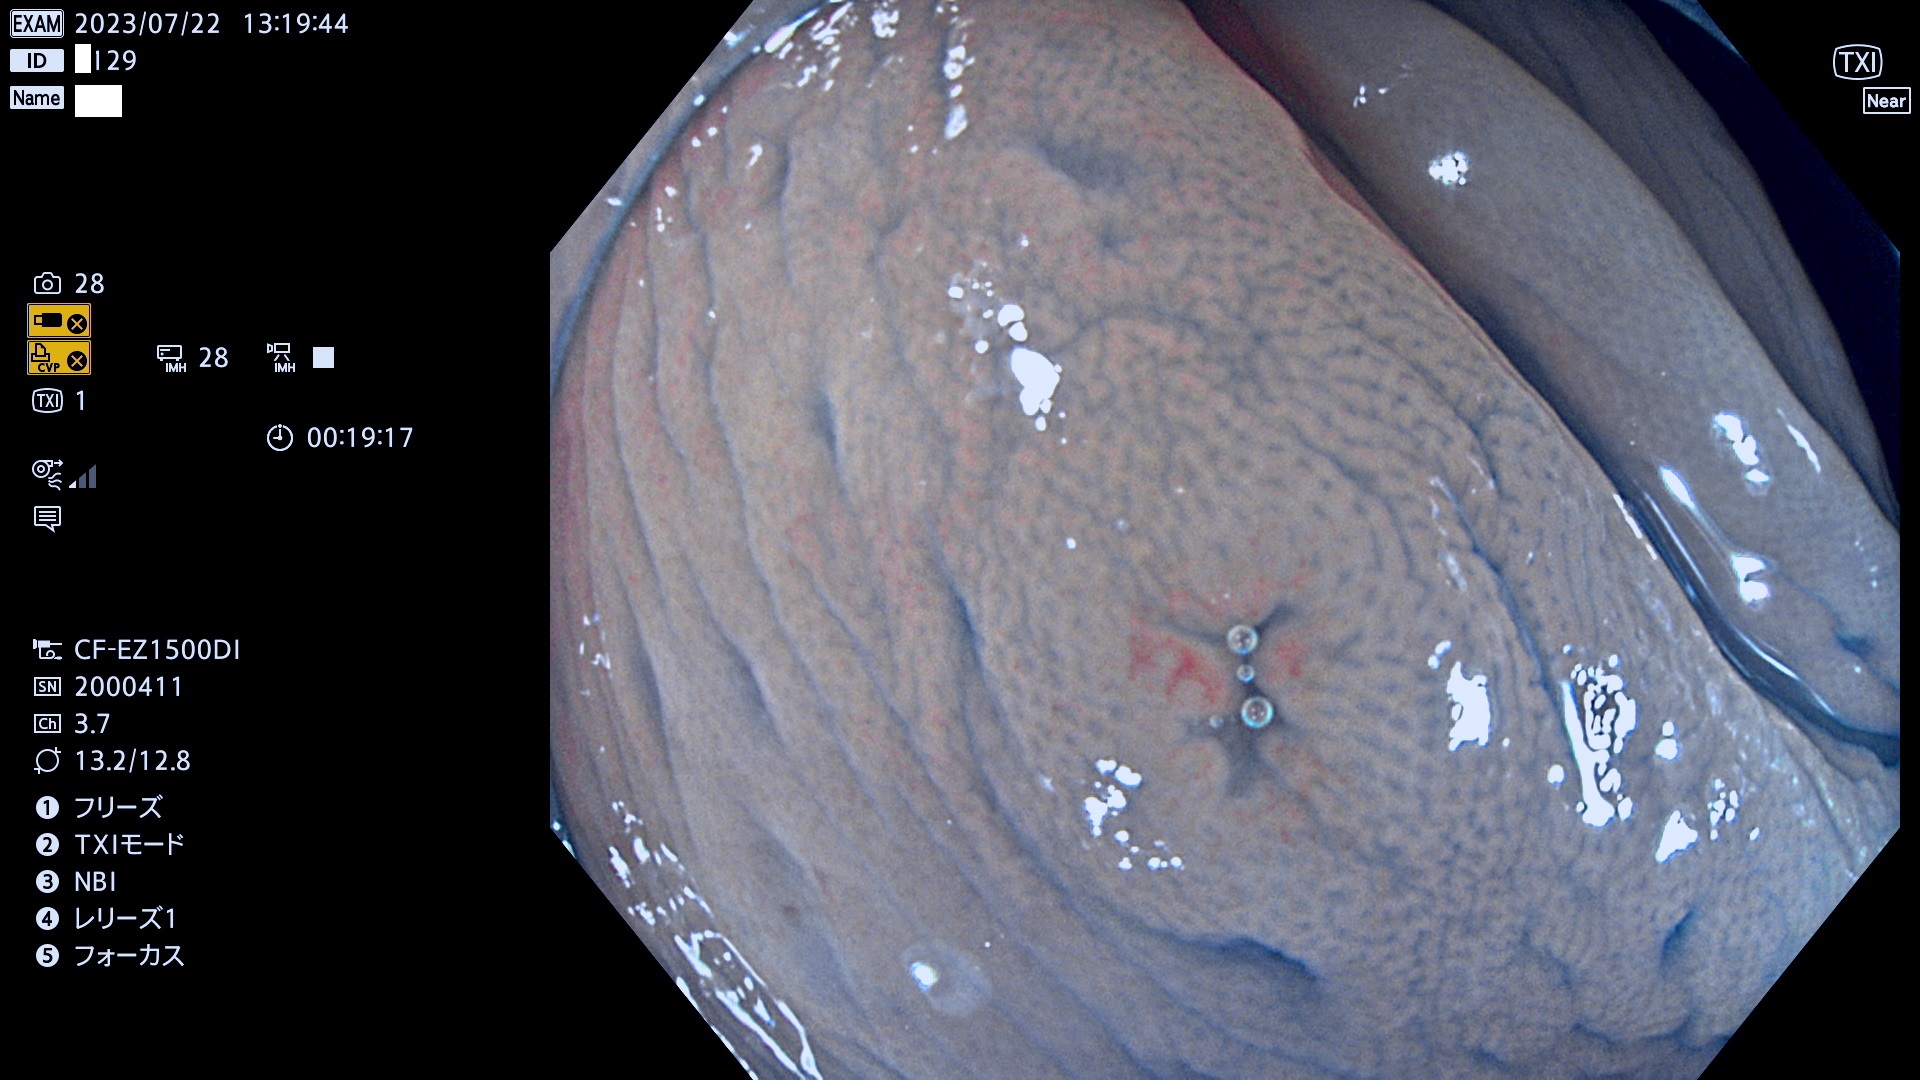

「表面型腺腫(Flat Adenoma)の中で、完全に平坦な物をUb、陥凹している物をUcと呼びます。平坦隆起型(Ua)よりも、発見が難しく危険な病変です。このタイプは「内視鏡後・大腸癌の重要犯人」であり、この発見率は「腺腫発見率」よりも、重要な意味があります。

毎週の検査(木・金・土・日)に発見されたUb、Uc型・腺腫を、その週の日曜の夜にUPし1週間、提示します。

抽出の対象期間 2023年7月20日(木)〜7月23(日)の4日間(48件の検査)12件